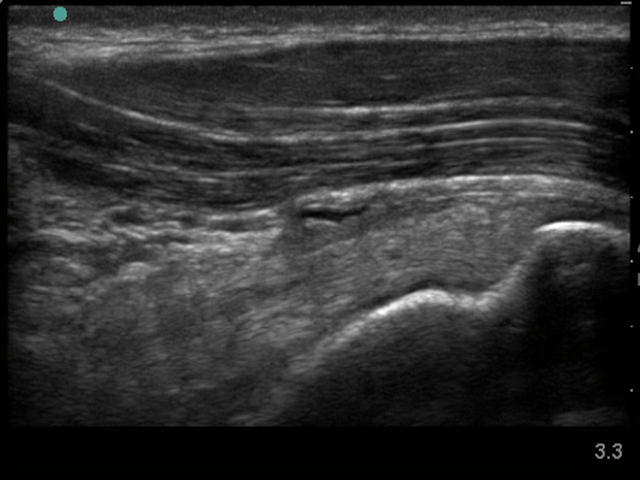

Imagen de engrosamiento de bolsa subdeltoidea del hombro